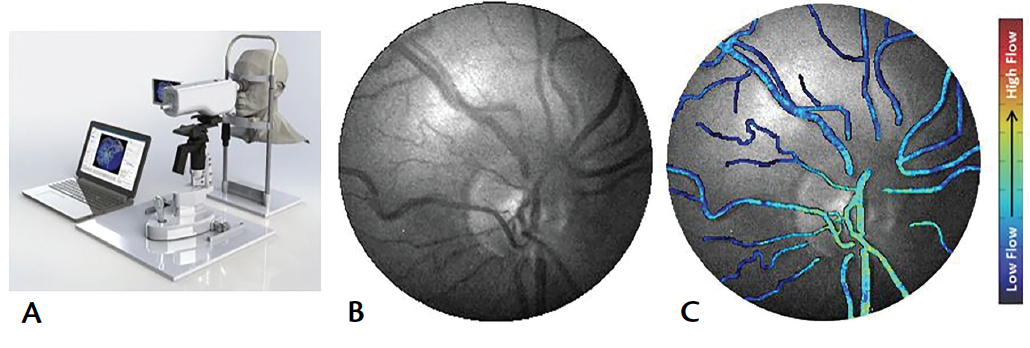

OCT angiography (OCTA) allows imaging of the perfused retinal vasculature by acquiring high speed, sequential OCT A-scans at the same retinal locus and then processing complex digital subtraction algorithms to analyze differences created by the moving columns of blood (Figure 3). A limitation of OCTA is that it does not provide imaging of vascular leakage or nonperfused vessels, and its imaging of new vessels might be imprecise. Distortion of the host retina, as with macular edema or atrophy, may also compromise image quality.

Photo courtesy of Gabor Mark Somfai, MD, PhD

Figure 3. View of CRVO using OCTA.

Laser speckle contrast imaging/flowgraphy visualizes and measures relative blood flow distribution based on speckle pattern measurements in real time (Figure 4).37-41 It has shown significant correlation with the flow modalities described above in rabbit and human retinas,42,43 and in CRVO treatment response.44

Images courtesy of Vasoptic Medical

Figure 4. Laser speckle contrast imaging (LSCI) XyCAM RI (Vasoptic Medical) retinal imaging device mounted on a slit-lamp base for fine motion adjustment (A). Fundus photograph taken with green light illumination (B). Fundus images of a healthy individual acquired using LSCI (C).